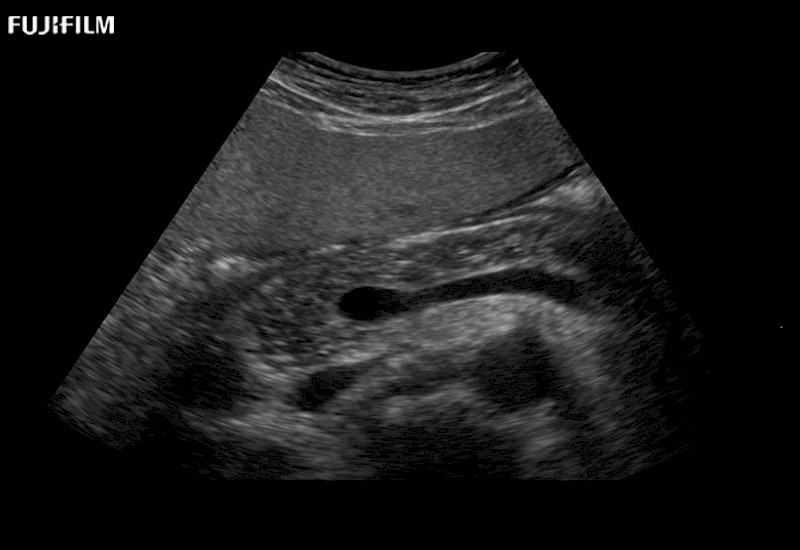

Learn moreFujifilm Healthcare continues to listen to the experts, our neurosurgeons, by developing an ultrasound system specifically designed for the Operating Room.

Guidance is the fundamental purpose for all of our surgical ultrasound technology. Fujifilm Healthcare is committed to designing tools that help neurosurgeons navigate inside the human body and provide the necessary information to immediately make critical surgical decisions.

With the ARIETTA Precision the next level of surgical ultrasound is here.